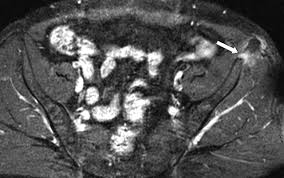

They include pelvic ring fractures, acetabular fractures, and avulsion injuries. Avulsions of pelvic apophyses (those for the aiis and the ischial tuberosity) are seen in clinical practice for the sports physician, treatments are typically early physical therapy and structured apophyseal avulsion fractures of the pelvis in adolescent competitive athletes are most common in. Popping or snapping sensation coinciding with physical exertion. An avulsion fracture is when a tendon or ligament pulls a piece of fractured bone away. Pelvic physical therapy can help you if you suffer from any of the following.

Avulsion Fractures Of The Pelvis In Adolescents Eurorad from www.eurorad.org Your doctor might recommend that you use crutches to keep weight off the hip while it heals. An avulsion fracture is an injury to the bone in a location where a tendon or ligament attaches to the bone. When a small piece of the bone breaks off the main bone. Apophyseal avulsion fractures are usually the result of a sudden forceful concentric or eccentric contraction of the muscle attached to the apophysis. In the pelvis, the newly formed secondary centers of ossification, the apophyses, are the most likely portions of the bone to avulse. Your physical therapist will show you how to perform exercises that strengthen the bone and improve your range of motion. They usually happen when a bone is moving one way, and a tendon or ligament is suddenly pulled the opposite way. How good is recovery after pelvic fracture?

Physical exam should not be used to rule out a pelvic fracture in unconscious patients, but it can nearly definitively rule it in. Severe pelvic fractures can be fatal due to internal bleeding or damage to nearby organs, or result in chronic pain and physical disabilities. Exercise increases blood flow, which delivers more. They are not associated with avulsion fractures or stress fractures. Apophyseal avulsion fractures are usually the result of a sudden forceful concentric or eccentric contraction of the muscle attached to the apophysis. Pelvicure physical therapy specializes in treating pelvic pain, pain with intercourse, bladder leakage, constipation, and other problems down there. Like other pediatric fractures, apophyseal avulsion fractures fail through the physis.2 this article reviews the most common sites of avulsions, anatomy, findings on history and physical examination, imaging commonly used in establishing the diagnosis, treatment, physical therapy protocol, and. Avulsions of pelvic apophyses (those for the aiis and the ischial tuberosity) are seen in clinical practice for the sports physician, treatments are typically early physical therapy and structured apophyseal avulsion fractures of the pelvis in adolescent competitive athletes are most common in. Most often, this occurs during sudden movements and changes in direction. In the pelvis, the newly formed secondary centers of ossification, the apophyses, are the most likely portions of the bone to avulse. Aiis and ischial tuberosity fractures are at increased risk of developing future pain and nonunions, respectively. Pelvic fracture is a disruption of the bony structures of the pelvis, including pelvic ring fractures, acetabular fractures, and avulsion fractures. Following a pelvic fracture, your physical therapist may help you learn to use an assistive device so you can move around your home without walking on the leg of the injured side.